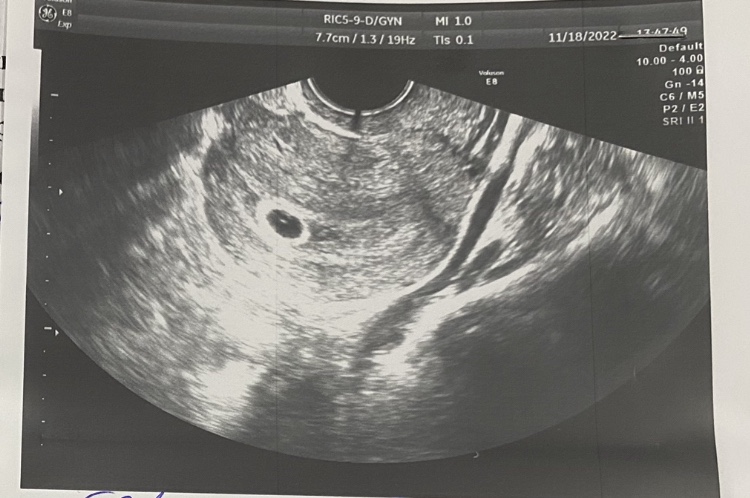

ХГЧ 5199 на 4 неделе беременности: норма или отклонение? Срок по УЗИ 4 недели 3 дня, делимся опытом!

17.11.22 ! Заветные ! Хгч 5199, срок по узи - 4 недели 3 дня!